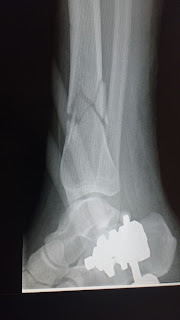

The rest of the night is lost to the labyrinth of trauma, but I know I had an MRI and a CAT scan. They told me I was lucky, and that it was almost a miracle that I’d only sustained injuries to my left leg. The leg in question, unfortunately, was in pieces, shattered like glass, and on top of that, my knee had cracked. It would need surgery, they said. They refused to give me any water, explain what surgery was needed, or introduce me to a doctor. I complained a lot. Andrew snuck me ice chips when my mouth got so dry it started frothing a little.

One surgery later, I was better in the sense that I was now partially a cyborg and also in excruciating pain.

See below for a fun album of my bone being broken and then (sorta) fixed (well... stabilized, anyway) via an external fixator! (Warning: mild gore.)